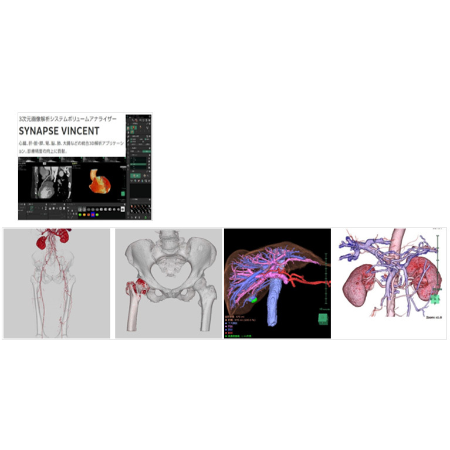

3次元画像解析システム | 富士フイルム |

SYNAPSE VINCENT |